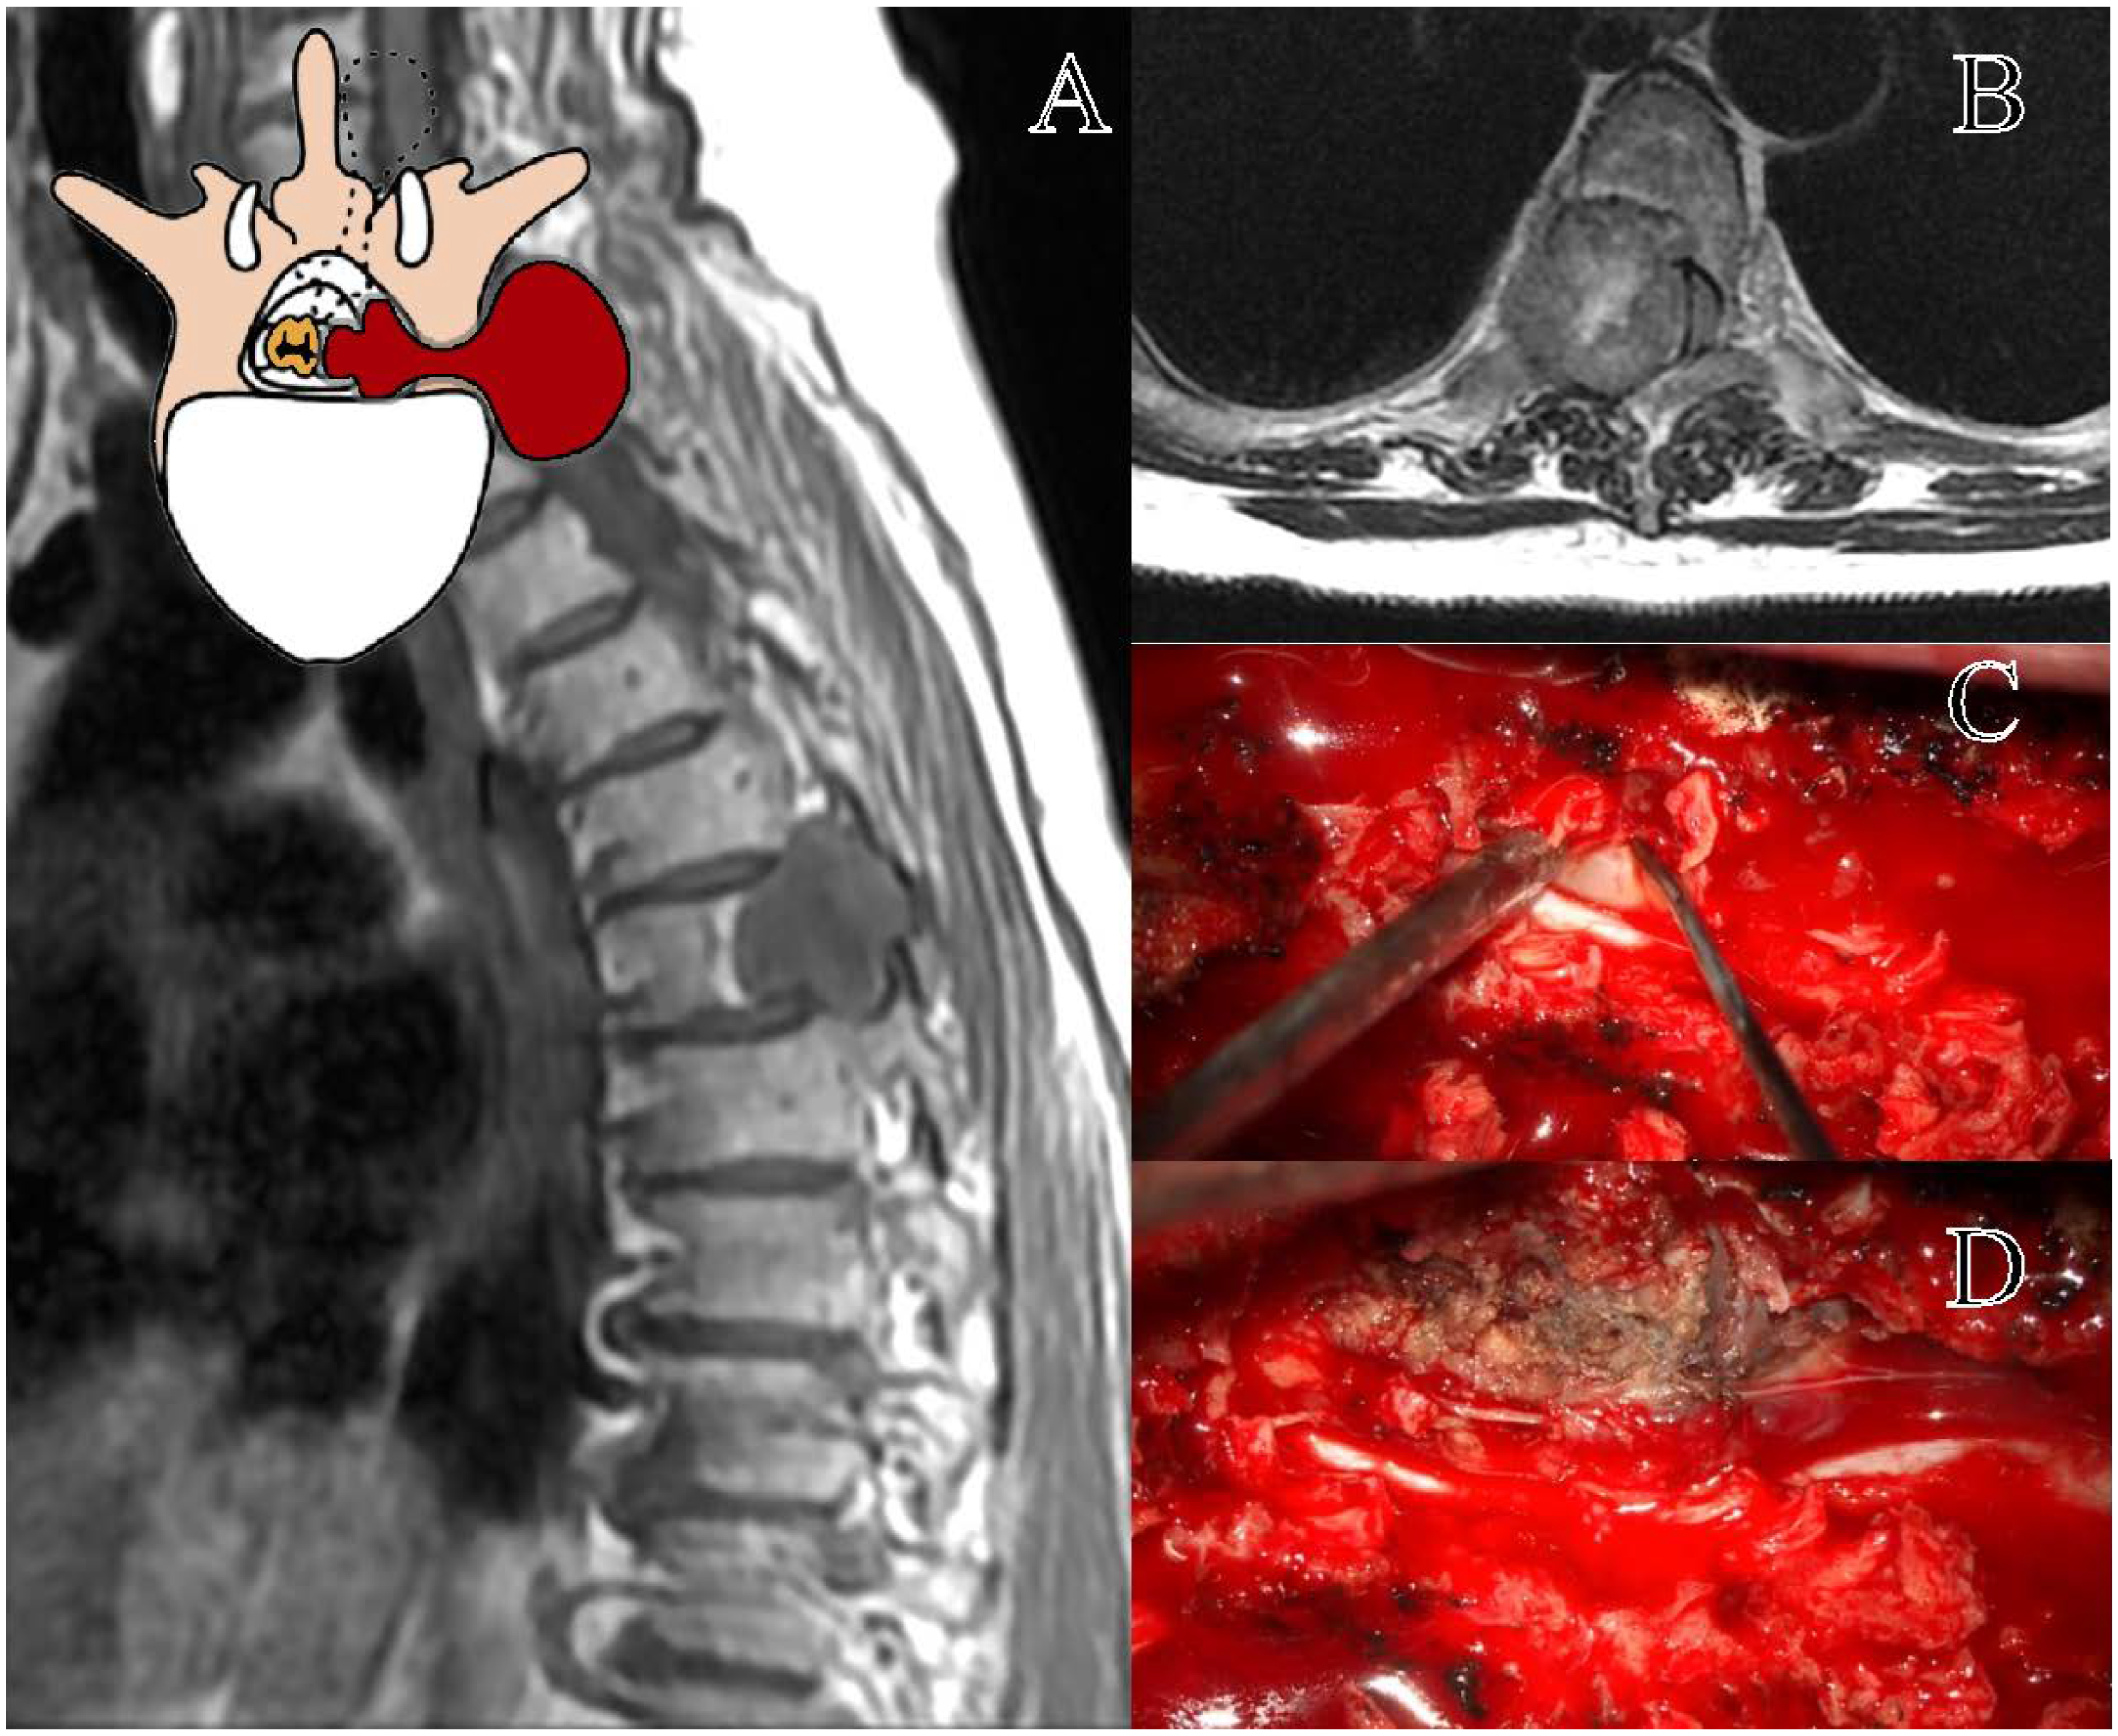

The Eden class I tumors, the intradural–intracanal lesions, were treated by HLCT or LCT. Recently, HLCT has been increasingly performed as a neurosurgical approach for these lesions, more than LCT [23], possibly due to its perceived advantages: it is considered less invasive, requires a shorter operative time [24], and does not lead to spinal instability, despite being more uncomfortable for the surgeon [25]. Our results, despite not considering spinal instability, suggest HLCT and LCT to be comparable for invasiveness, blood loss, and surgical time. A major limitation of our study is the lack of a direct evaluation of postoperative spinal instability. Noteworthy, in our multicenter series, no patients were primarily or secondarily stabilized. It is important to note that the concept of spinal stability in the thoracic region differs from that of the lumbar and cervical spine [26]. However, in our opinion, these two techniques are substantially equivalent for the surgical management of thoracic schwannomas. The softness of the lesion allows for both ‘en bloc’ and piecemeal resection, with the main structure to be preserved being the spinal cord, which at the thoracic level permits only a gentle retraction (Figure 1) [20,27,28]. Accordingly, we advocate for the use of the traditional bilateral LCT for these lesions. Further larger and prospective studies are needed to better elucidate the impact of these surgical techniques on thoracic spinal stability.

Figure 1. Representation of a T11–T12 thoracic schwannoma, Eden Type I. (A) Preoperative sagittal T1-weighted MRI with contrast, highlighting an intradural-extramedullary lesion at the T11–T12 level, located in the midline and right paramedian region, with peripheral contrast enhancement. (B) Axial scan showing the localization of the lesion. (C) Intraoperative view of dural exposure after laminectomy, with a detail of the lesion. (D) Microsurgical dissection and tumor removal, with identification of the thoracic nerve root of origin, which will be sacrificed.